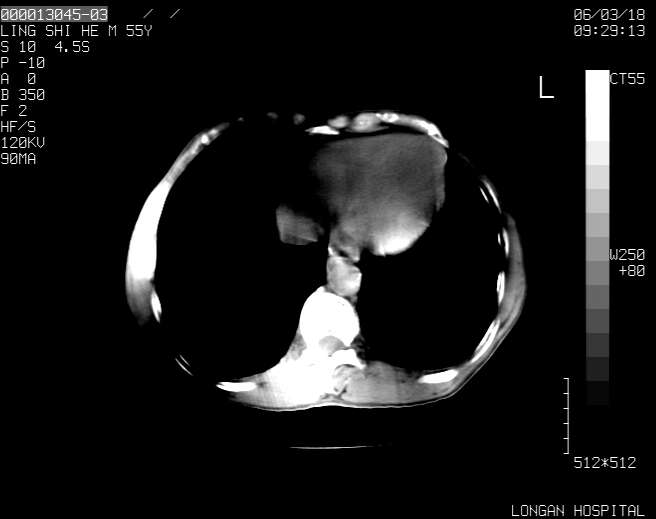

以下是引用guzhongliangddd在2006-3-21 22:13:00的发言:[br]病灶主要位于肝右叶的后份,内见异常血管,门脉主干及右支受侵{提示有癌栓形成},门腔间隙内见增大淋巴结。肝左叶内未见异常。

以下是引用zhuxinli在2006-3-22 1:23:00的发言:[br][br] 病灶主要位于肝右叶的后份,内见异常血管 .门脉右支截断,右叶前段早期强化(考虑动静脉漏),腹膜后肿大淋巴结,病灶逐渐强化,考虑为胆管细胞癌[br]